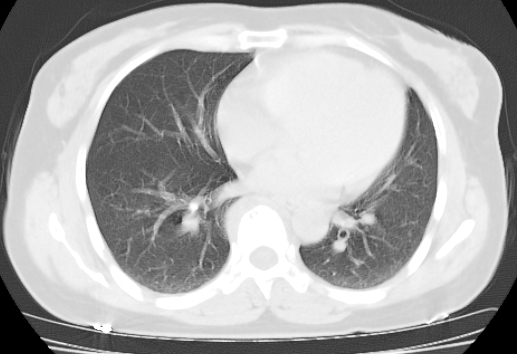

标题: CT25227:背部疼痛伴双侧胸壁痛2月,食欲差。 [打印本页]

标题: CT25227:背部疼痛伴双侧胸壁痛2月,食欲差。

肺结核并胸椎结核?请各位高手指教。

考虑胸椎结核并椎旁软组织肿胀。

考虑胸椎结核并椎旁软组织肿胀。 支持